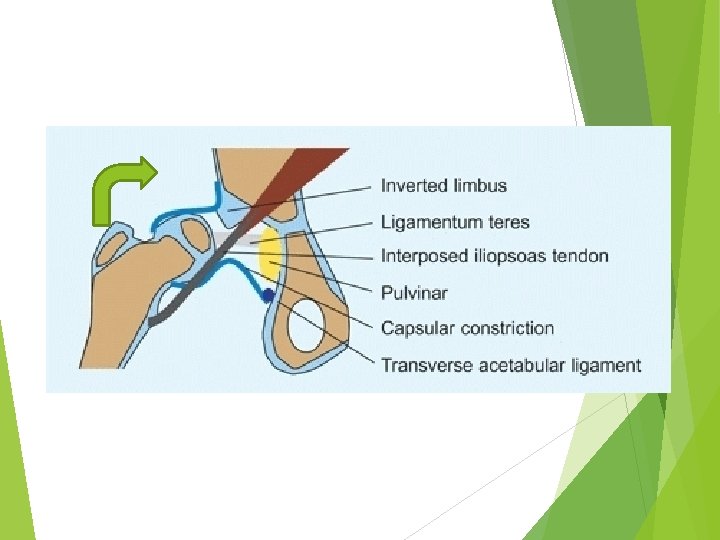

Factors that prevent reduction 1 -Redundant capsule but constricted ? ? ? 2 -elongated ligamentum teres 3 -Tight abductor muscle 4 -fibrouse tissue in the socket (Pulvinar) 5 -inverted labrum (limbus) 6 -Transverse Acetabular ligament 7 -interposed iliopsoas tendon